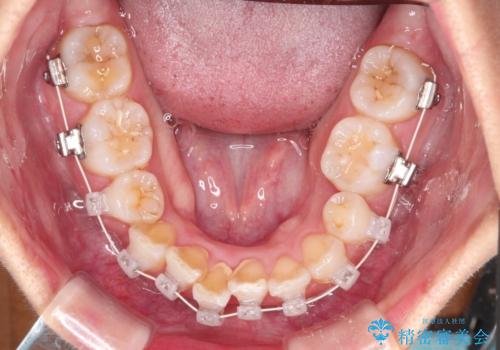

- 矯正装置

- 審美装置

- 前歯の凸凹を主訴に来院されました。

抜歯を行い、ワイヤー矯正にて治療を行いました。

凸凹もなくなり、歯磨きもしやすくなったと喜んでいただきました。

CTにて骨を確認し、側切歯の歯根をこれ以上頬側に出せないことを確認しています。